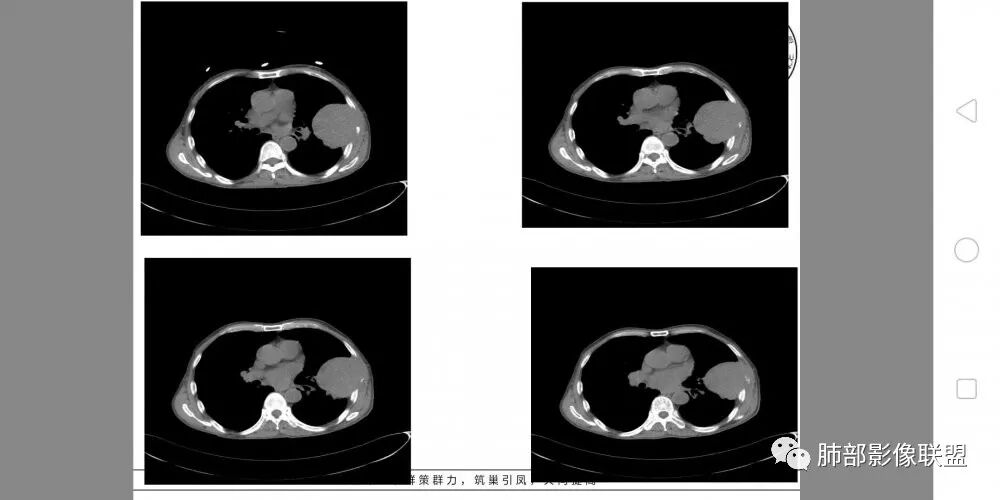

老年男性,外伤入院,“左上肺”实性肿块,边缘光滑,突破壁层胸膜并侵犯肋骨及肋间肌,增强扫描轻度强化,可见明显坏死。

• 患者老年男性,因摔伤致腰部、双侧髓部疼痛2月余就诊

• 胸CT:左肺上叶实性占位,病灶与支气管无关,病灶对斜裂挤压,病灶周围光滑,未见分叶、毛刺;纵隔窗可见病灶内低密度区,病灶对胸壁侵袭,并可见肋骨破坏。

患者中老年男性,外伤后入院。胸部CT:左肺上叶实性肿块,近心侧边界清楚,边缘光滑,胸壁侧突破壁层胸膜、肋间隙并侵犯肋骨及肋间肌,增强扫描轻度强化,可见近心侧多发片状坏死,未见明显淋巴结肿大。综合考虑SFT,鉴别肉瘤及结核。

老年男性,外伤入院。

胸CT:左上肺实性大肿块,边缘光滑,突破胸膜侵犯肋骨及肋间肌,纵隔淋巴结肿大,增强呈轻度强化,可见明显片状坏死。

定位:主体病灶在肺内,外朝内,可见支气管推移,胸膜掀起未见,巨大肿物未见肿物边缘有肺不张条状高密度影,推测肺内可能大。

老年男性,腰部外伤史。

胸部CT所见左肺上叶尖后段胸膜下较大山丘形肿块,边界清楚,宽基底与胸膜相贴,边缘与胸膜呈直角及锐角相交。邻近上叶尖后段支气管受压推挤,叶裂局部膨隆,病灶周围见少许磨玻璃密度影,边界不清。纵膈窗显示,肿块密度均匀,增强扫描呈不均匀轻度强化,邻近肋骨骨质破坏,病变沿肋间隙向外侵犯,局部胸膜增厚。纵膈内见多发小淋巴结,未见胸腔积液征象。综合考虑恶性占位,肉瘤样癌可能性大。腰椎及髋部考虑骨转移。